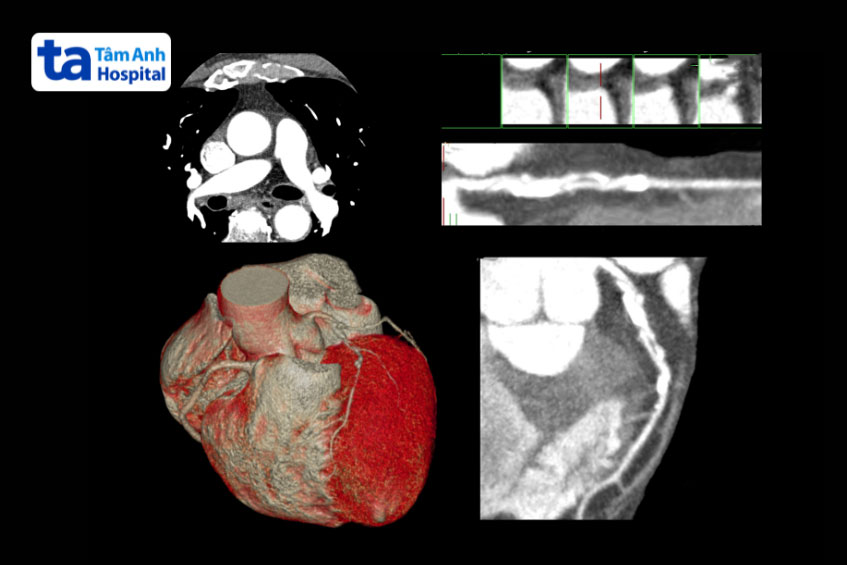

Để chẩn đoán phình động mạch vành, bác sĩ sẽ hỏi chi tiết về các triệu chứng của người bệnh cũng như tiền sử bệnh cá nhân và gia đình. Ngoài ra, các phương pháp chẩn đoán hình ảnh chuyên sâu thường được thực hiện, bao gồm: (3)

Đặc biệt, phương pháp phổ biến và hiệu quả nhất để chẩn đoán chính xác phình mạch vành là chụp mạch vành kết hợp siêu âm nội mạch.

Sự kết hợp các công nghệ hiện đại không chỉ giúp chẩn đoán chính xác mà còn hỗ trợ bác sĩ đưa ra phương án điều trị phù hợp nhất, từ đó giảm nguy cơ biến chứng và cải thiện sức khỏe tim mạch cho bệnh nhân.